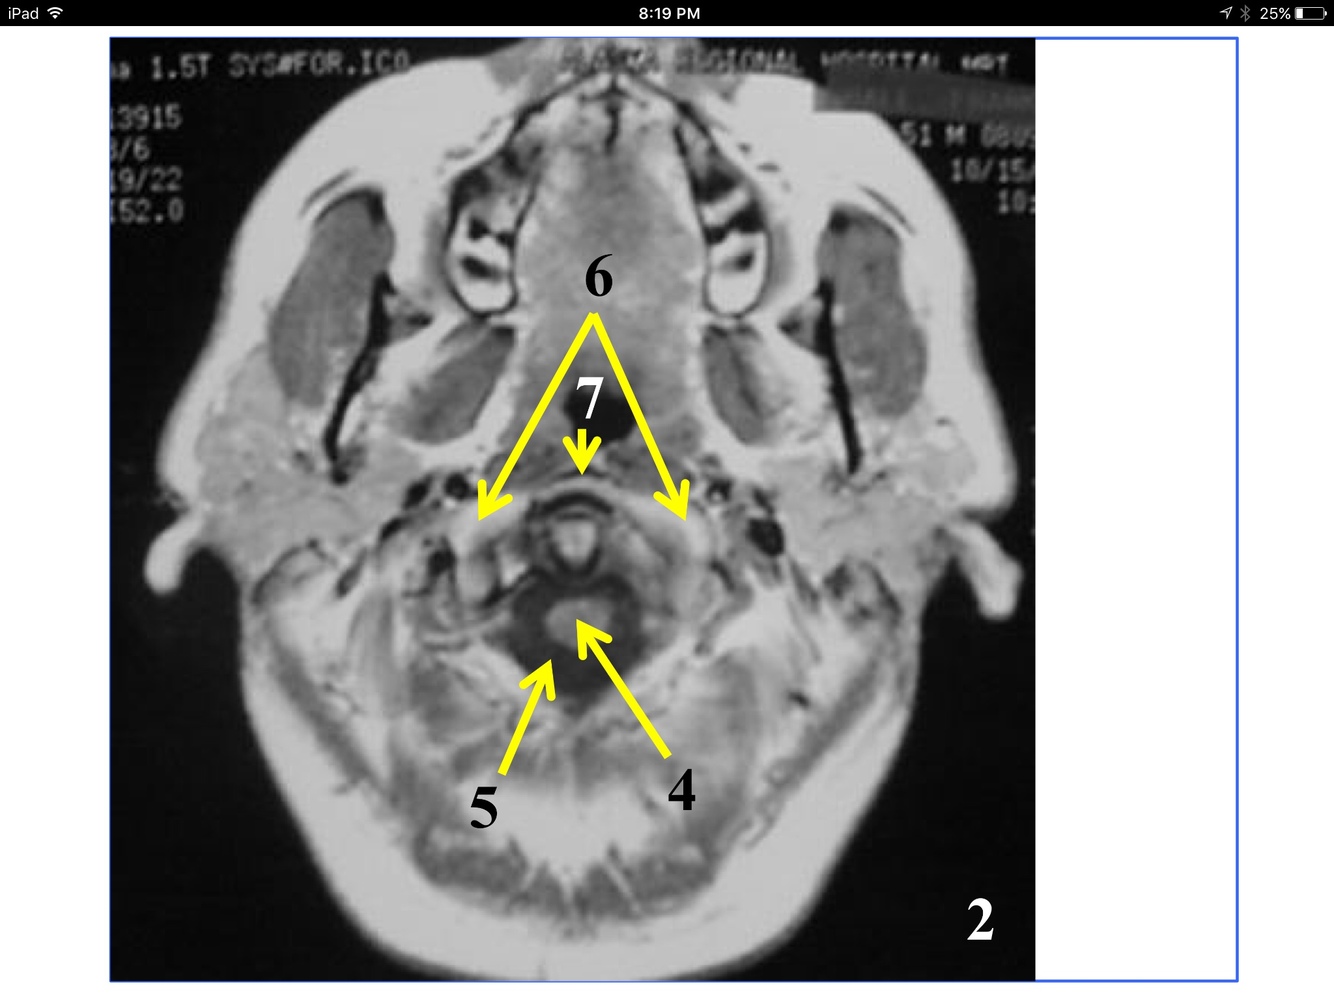

*near the atlantooccipital joint

**the tubercle of the anterior arch is where teh arrow is pointing, but not seen here.